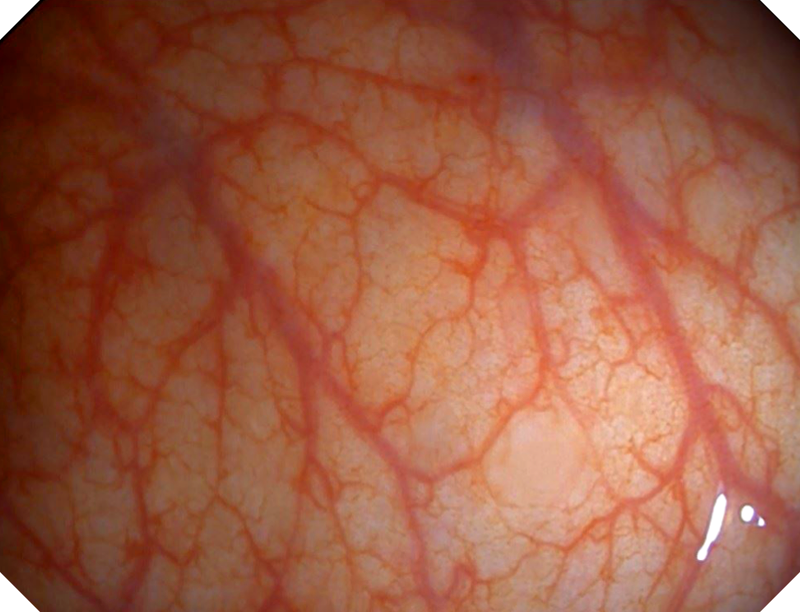

SFI图像

SFI图像

VIST图像

VIST图像